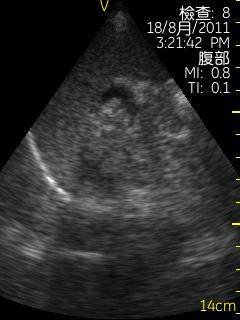

Vscan临床图片 腹部